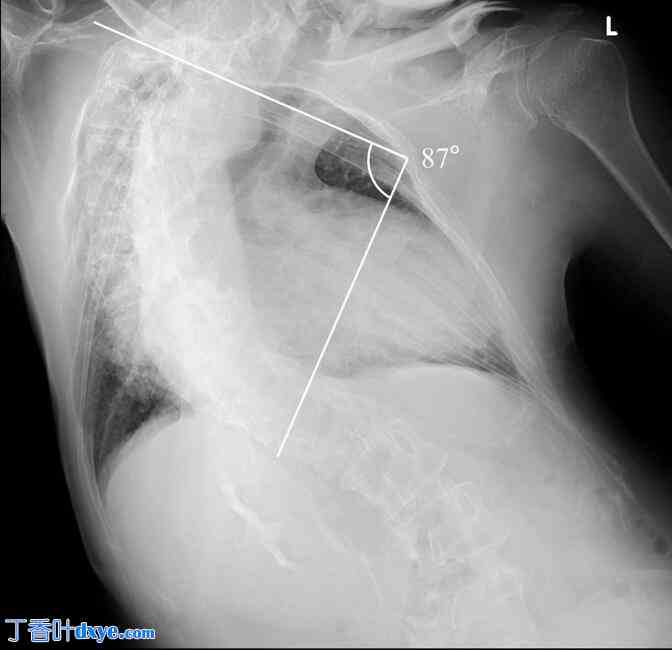

图1.

患者患有严重的脊柱侧弯。脊柱弯曲在中胸段食管水平向右凸,在下段食管水平向左凸,Cobb角为87°。